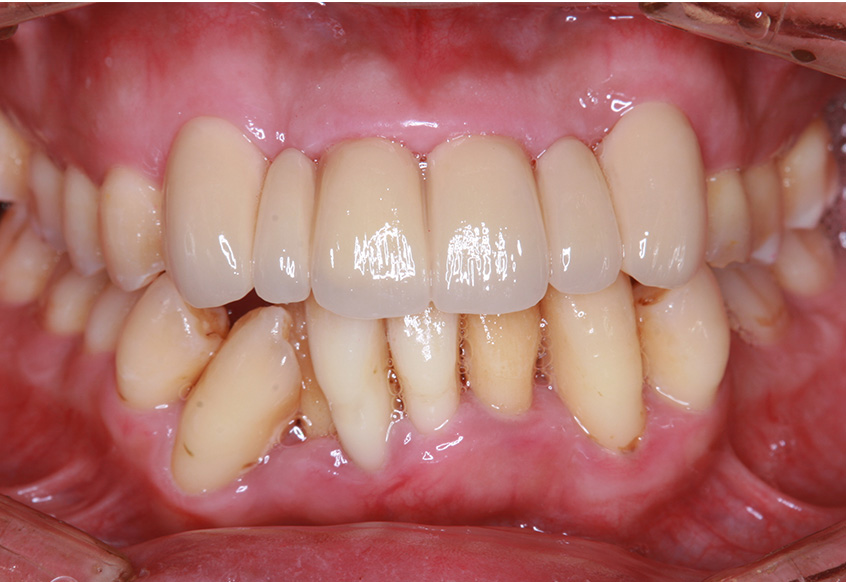

6ヵ月経過すると、矯正治療を終了し、前歯に被せ物の治療を行いました。

最初のお口の中 2025/3/22

被せ物装着

| 治療内容 | 上顎側切歯を2本抜歯した後、上顎の歯にブラケットを装着し、ワイヤー、矯正用ゴムで歯の移動を行いました。その後、被せ物の治療を行って治療を終了しています。 |